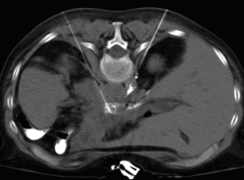

Die durchleuchtungs- und computertomographie-gesteuerte periradikuläre, epidurale und intradiskale Schmerztherapie (PRT) wird im Institut für Radiologie der Augusta-Kranken-Anstalt häufig zur Behandlung von Bandscheibenvorfällen, entzündlichen und degenerativen Bandscheibenveränderungen an den Segmenten der Lenden- (Abb. Links) und Halswirbelsäule (Abb. Mitte Links) , seltener auch an der Brustwirbelsäule eingesetzt. Unter bildgebender Kontrolle wird in örtlicher Betäubung eine dünne Hohlnadel an die Nervenwurzeln oder in die Bandscheibe im erkrankten Wirbelsäulenbereich vorgeschoben. Durch die Kontrolle in der CT wird eine millimetergenaue Platzierung der Nadel erlaubt. Durch eine simultane Kontrolle mittels Durchleuchtung (C-Bogen am CT) gelingen auch schwierige Positionierungen z.B. im Segment L5/S1 (Abb. Mitte Rechts). Die korrekte Nadellage wird jeweils durch Gabe von 0,5 ml Kontrastmittel überprüft, wobei auf eine Anfärbung der epiduralen Räume (bzw. bei intradiskaler Therapie auf eine Kontrastierung des Gallertkernes der Bandscheibe) Wert gelegt wird (Abb. Rechts).